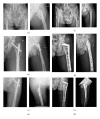

Internal fixation of intertrochanteric hip fractures: a clinical comparison of two implant designs

Objective: To compare two internal fixation devices clinically in stabilisation of intertrochanteric femur fractures.

Methods: Eighty-seven patients were randomised upon their admission to the hospital using a sealed envelope method. Forty-five were treated with proximal femur nail antirotation (PFNA) and 42 with reverse less invasive stabilisation system (LISS). The perioperative data were recorded and compared in relation to fracture type.

Results: In each type of fractures, no significant differences were found with respect to the blood loss, the quality of reduction, the time to bony healing, and the Harris hip score between the 2 groups. The mean duration of surgery was significantly longer in reverse LISS group than in PFNA group.

Conclusion: Both the PFNA and the reversed LISS are effective in the treatment of different types of intertrochanteric femur fractures. PFNA is superior to reverse LISS in terms of surgical time, weight-bearing, and perhaps fluoroscopy time.